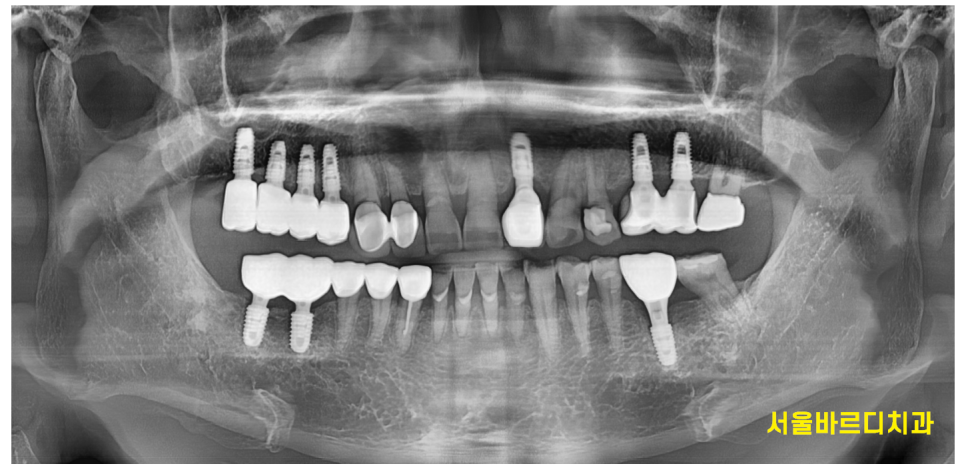

물론 임플란트나 보철을 많이 할 경우

치아 교정에 제약이 있는 것은 맞습니다.

240924

치아 교정은 치아 뿌리를 움직여 하는데

임플란트는 뼈에 고정되어있잖아요~

그래서 개수가 많으면 치아 교정 어렵긴 합니다.

그렇지만 불가능한 것은 아니에요!

x-ray, 구강 상태, 교합 확인

다양한 검사를 시행